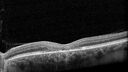

Latanoprost induced CME20 views89 year old man with CME from latanoprost that cleared within one month of stopping the medicationNov 23, 2025

Latanoprost induced CME25 views89 year old man with CME from latanoprost that cleared within one month of stopping the medicationNov 23, 2025

Latanoprost induced CME22 views89 year old man with CME from latanoprost that cleared within one month of stopping the medicationNov 23, 2025

Latanoprost induced CME26 views89 year old man with CME from latanoprost that cleared within one month of stopping the medicationNov 23, 2025

Latanoprost induced CME33 views89 year old man with CME from latanoprost that cleared within one month of stopping the medicationNov 23, 2025

Latanoprost induced CME30 views89 year old man with CME from latanoprost that cleared within one month of stopping the medicationNov 23, 2025

Latanoprost induced CME16 views89 year old man with CME from latanoprost that cleared within one month of stopping the medicationNov 23, 2025

Latanoprost induced CME24 views89 year old man with CME from latanoprost that cleared within one month of stopping the medicationNov 23, 2025

Latanoprost induced CME37 views89 year old man with CME from latanoprost that cleared within one month of stopping the medicationNov 23, 2025

Latanoprost induced CME36 views89 year old man with CME from latanoprost that cleared within one month of stopping the medicationNov 23, 2025